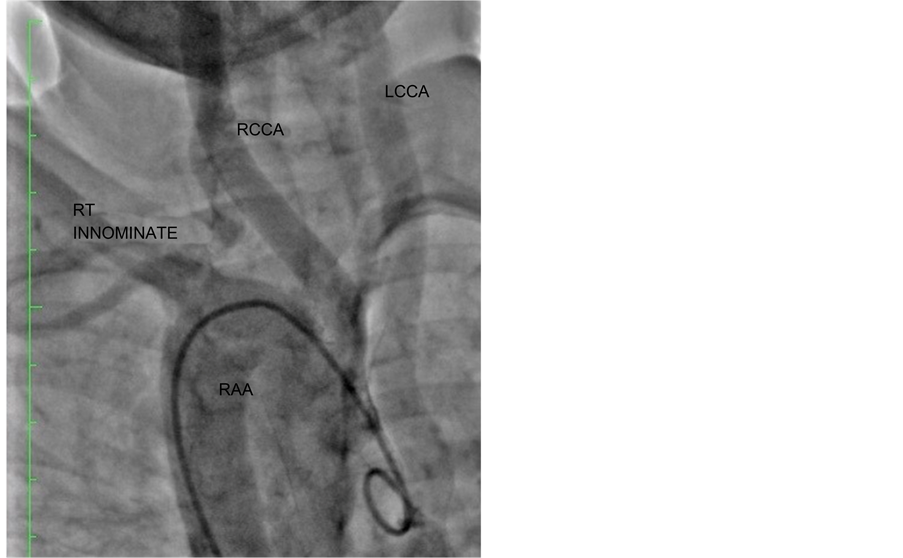

An 8-year-old child presented with bluish discolouration of lips and fingers since 3 - 4 months of his birth along with features of recurrent Lower Respiratory Tract Infection (LRTI). There was no history of cyanotic spells, weakness of any limbs, pain or numbness. There was no history suggestive of cerebral, vertebral or basilar insufficiency. On examination, patient had mild cyanosis and clubbing of fingers. Pulses in the left upper limb were weaker as compared to that in the right upper limb; however there was no significant blood pressure difference (Right (Rt) = 90/52 mm Hg, Left (Lt) = 87/50 mm Hg). Saturation of oxygen (Spo2) in Rt upper limb was 87% and that in Lt upper limb was 84%. Lower limb pressures and O2 saturation were also comparable with no significant differences. Cardio-vascular System (CVS) examination revealed a pansystolic murmur at apex. Chest X-ray showed a RAA with boot-shaped heart. Echocardiographic study revealed a typical anatomy consistent with TOF. There was sub aortic VSD with right ventricular outflow tract obstruction (RVOT) and pulmonary stenosis. Cardiac catheterization confirmed TOF with confluent and adequate Pulmonary Artery’s (PA’s). Aortogram confirmed the RAA with normal Right innominate, Right common carotid artery (RCCA) and Left common carotid artery (LCCA) with non visualization of LSCA; suggestive of isolation of LSCA (Figure 1). CT angiography confirmed the origin of LSCA from LPA (Figure 2) through an atretic Patent Ductus Arteriosus (PDA) and the LSCA was filling via a collateral artery originating from the descending aorta.

Figure 1.Cath study showing Rt Innominate artery, RCCA and LCCA originating from RAA with the non visualization of LSCA which itself indicate isolation of LCSA (a) and LSCA originating from LPA with collaterals from descending aorta (b).